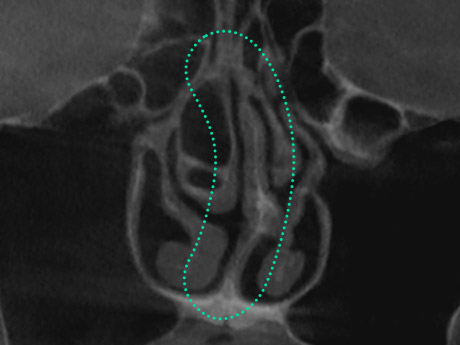

Crooked Nose Surgery is a procedure to straighten a deviated nose

caused by structural internal issues or trauma leading to asymmetry

of the bone or cartilage. Depending on the severity of the deviation,

a crooked nose can affect breathing, causing discomfort. Through

3D-CT scans, it is determined whether the deviation stems from

internal cartilage or is simply an external appearance issue. Accurate

diagnosis is essential, followed by a customized surgical approach

to properly correct the condition.

Crooked Nose Surgery is a procedure to straighten a

deviated nose by using 3D-CT to accurately diagnose

whether the cartilage inside is bent or if the deviation

is only visible externally, followed by a customized

surgical method tailored to the condition for proper

correction.

A crooked nose often involves not only the visible appearance but also the internal nasal structure.

Common types, including C-shaped, S-shaped, and diagonally shaped deviations, often accompany functional issues like septal deviation or nasal

valve stenosis, requiring precise 3D-CT and nasal endoscopy examinations to determine the cause and apply tailored solutions.

A crooked nose often involves deviations in the internal

nasal structure, with common types including C-shaped,

S-shaped, and diagonally shaped forms, frequently

accompanied by functional issues ike septal

deviation or nasal valve stenosis, making it crucial to identify

the exact cause.